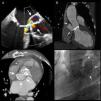

In the present hospitalization he was diagnosed with S. epidermidis prosthetic endocarditis. The echocardiogram showed severe mitral regurgitation and AR secondary to periprosthetic leakage, as well as a large cavity posterior to the aortic arch communicating with the prosthetic dehiscence and with the aorta (Figure 1A). Multislice computed tomography (CT) identified the structure as a saccular aneurysm and its neck (Figure 1B and C). Aortography (Figure 1D) confirmed the findings of a large aneurysm and severe AR. After 8 weeks of antibiotic therapy the patient underwent further surgery, a mechanical mitral-aortic valve being implanted and the aneurysm being excluded with a Dacron patch.

Prosthetic infection and periannular extension are serious complications of endocarditis. In this patient, repeated bacterial infections led to dehiscence of the prosthesis, severe AR and the formation of a large mycotic aneurysm. CT angiography and aortography established the anatomical diagnosis and the size and extent of the aneurysm, enabling appropriate surgery to be scheduled.